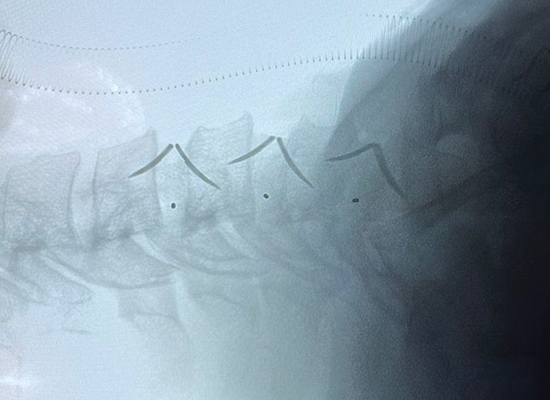

Intraoperative Imaging

Intraoperative view of Uni-C Standalone Cervical Cage placement during anterior cervical fusion by CZMEDITECH 1

Intraoperative view of Uni-C Standalone Cervical Cage placement during anterior cervical fusion by CZMEDITECH 2